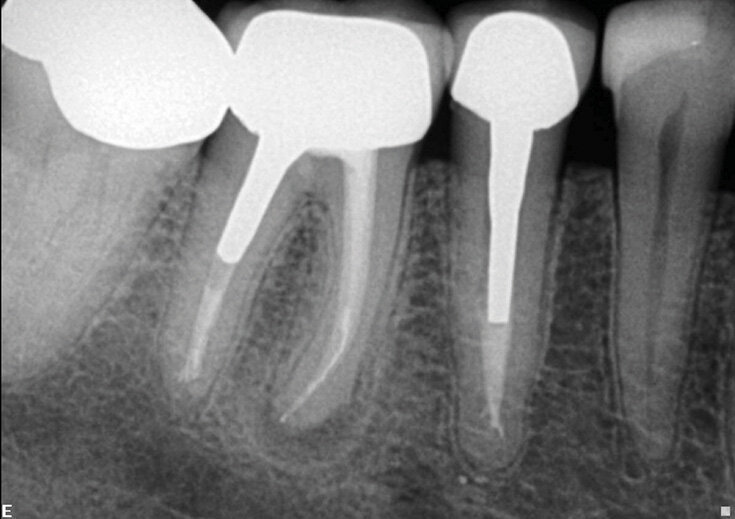

Slučaj 2 – Slika br. 4: Inicijalni periapikalni Rtg snimak

Slučaj 2 – Slika br. 5: Periapikalni kontrolni Rtg snimak odmah nakon tretmana

Slučaj 2 – Slika br. 6: Periapikalni kontrolni Rtg snimak nakon godinu dana od tretmana

Pacijent je upućen na retretman donjeg molara. Početni rendgenski snimak prikazuje metalni liveni kočić u distalnom kanalu, separiran instrument u jednom od mezijalnih kanala i radiolucenciju na apeksu. Pacijent je obavešten da ću morati da mu uklonim staru krunicu i metalni kočić da bih mogao da uradim enododntski retretman i to će mi omogućiti pristup kanalima korena da ih ponovo obradim i napunim. Alternativa je da bila da uradim mikrohirurgiju na mezijalnom korenu, ali za ovo bih morao da isečem dugačak deo korena da bih postigao hermetičko zatvaranje unutar kanala zbog zalomljene turpije i nedostajućeg dela kanala koji nije tretiran. Pacijent je prihvatio prvi izbor. Prvi koraci su bili sečenje krunice i njeno uklanjanje, zatim sam nastavio sa delikatnim sečenjem metalnog kočića kako bi ga uklonili deo po deo. Deo zuba u kojem je kočić sam vibrirao ultrazvukom i bezbedno ga skidao. Ovo mi je omogućilo pristup gutaperki ispod. Koristio sam isti redosled turpija, Traverse i Zenflex. U distalnom korenu sam uspeo da idem sve do radne dužine, u mezio-bukalnom takođe do kraja, u mezio-lingvalnom sam stao gde je bila separiran isntrument. Ovde sam počeo da koristim male K-file turpije veličina 06 08 10 i 15 da zaobiđem instrument, imao sam sreće da to uradim pa čak i da je izvadim iz unutrašnjosti zakrivljenosti, i napravljeno je potpuno čišćenje i oblikovanje, praćeno 3D obturacijom sa elements IC (Slika br. 4). Jednogodišnje praćenje (Slika br. 5) pokazuje odlično izlečenje.